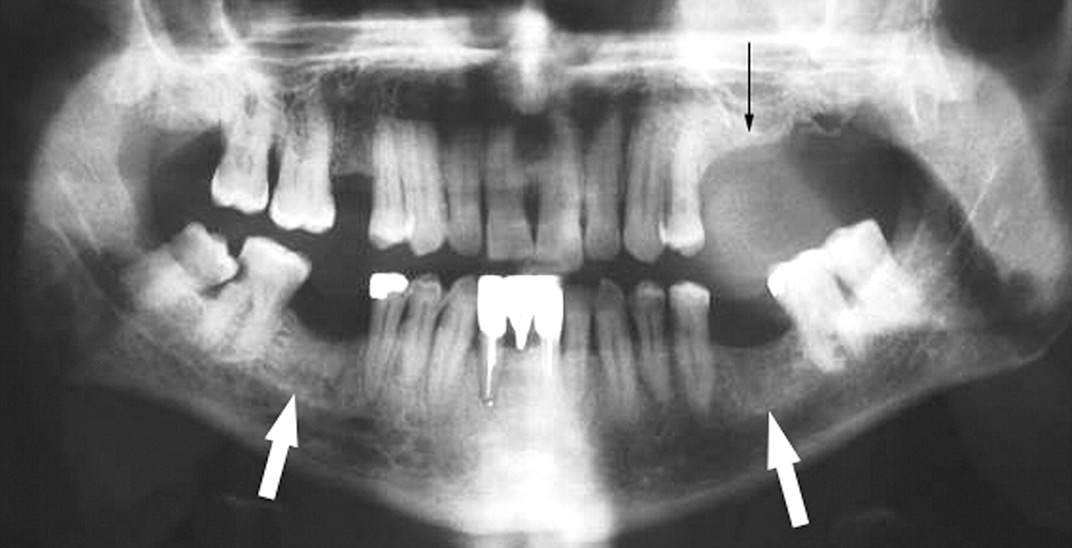

Медицинские Исследования: Кортикальная Пластинка на ОПТГ